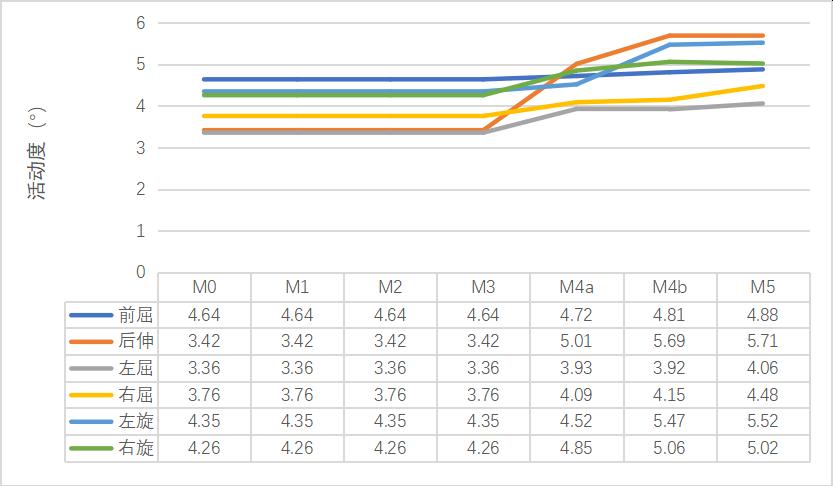

1����、正常有限元模型(M0)L3-4节段在前屈���、后伸�����、左屈����、右屈����、左旋���、右旋的活动度为4.12°����、3.2°����、3.04°����、3.02°����、3.23°�����、3.38°��;L4-5节段在前屈�����、后伸���、左屈����、右屈��、左旋����、右旋的活动度为4.46°���、3.42°��、3.36°�����、3.76°��,4.35°���,4.26°��。与文献比较���,模型中各节段不同状态活动度数据均在正常范围之内���,证明该模型基本符合人体实验����,可用于有限元相关研究��。

2����、0-2级成型(M1-M3)因没有进行骨质的切除��,所以对腰椎稳定性没有明显的影响����。3-4级成型时(M4a���、M4b�����、M5)����,L3-4节段在左旋及右旋时的活动度变化最大���,其中左旋由24.15%增加到30.34%����,右旋由27.81%增加到91.42%���,在前屈及左旋时的椎间盘应力值变化最明显���,其中前屈由13.64%增加到31.82%��,左旋由13.33%增加到31.33%��。L4-5节段在后伸时的活动度变化最大��,由46.49%增加到66.96%���,在前屈时的椎间盘最大应力值变化最大����,由19.12%增加到37.50%���,见表3-8��。

(1)活动度变化

表格 3 成型后L3-4节段活动度变化

表格 4 成型后L4-5节段活动度变化